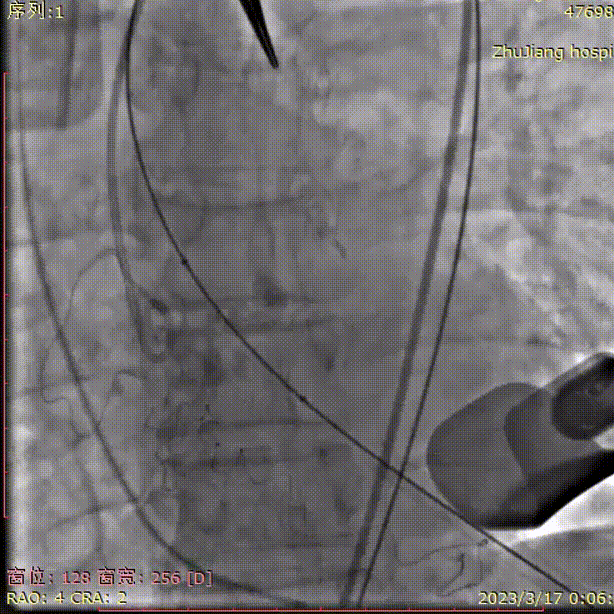

球囊预扩张,无漏,双侧冠脉显影良好:

定位件入窦,瓣膜件下落到瓣环平面,造影确认位置: